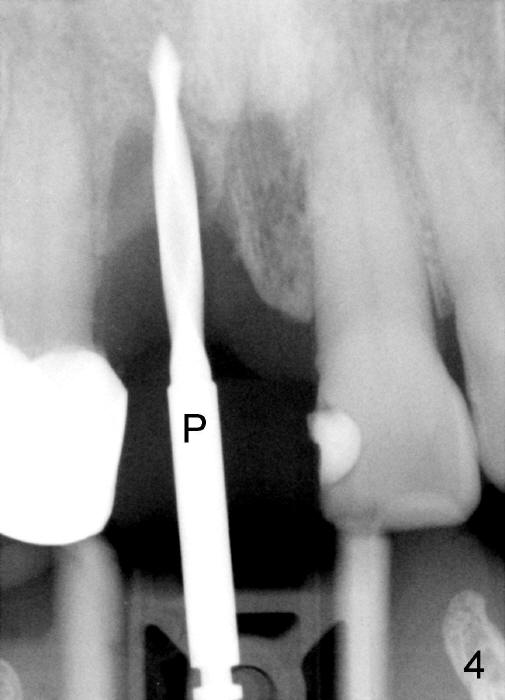

A 64-year-old lady requests replacing #7 and 8 crowns (Fig.1,2). When #8 is extracted, the labial plate is found to be missing (Fig.3). Following 2 mm pilot drill (Fig.4,5 P), 3.8 mm tap drill (Fig.6,7 T) and 4.5x14 mm implant (Fig.8 I) and 4.8 mm abutment (Fig.9 A), corticocancellous bone is harvested from the left tuberosity and placed in the labial gap of the socket (Fig.10 G). Collagen dressing is placed over the bone graft (Fig.11 C). The former is secured in place by an immediate provisional (P).